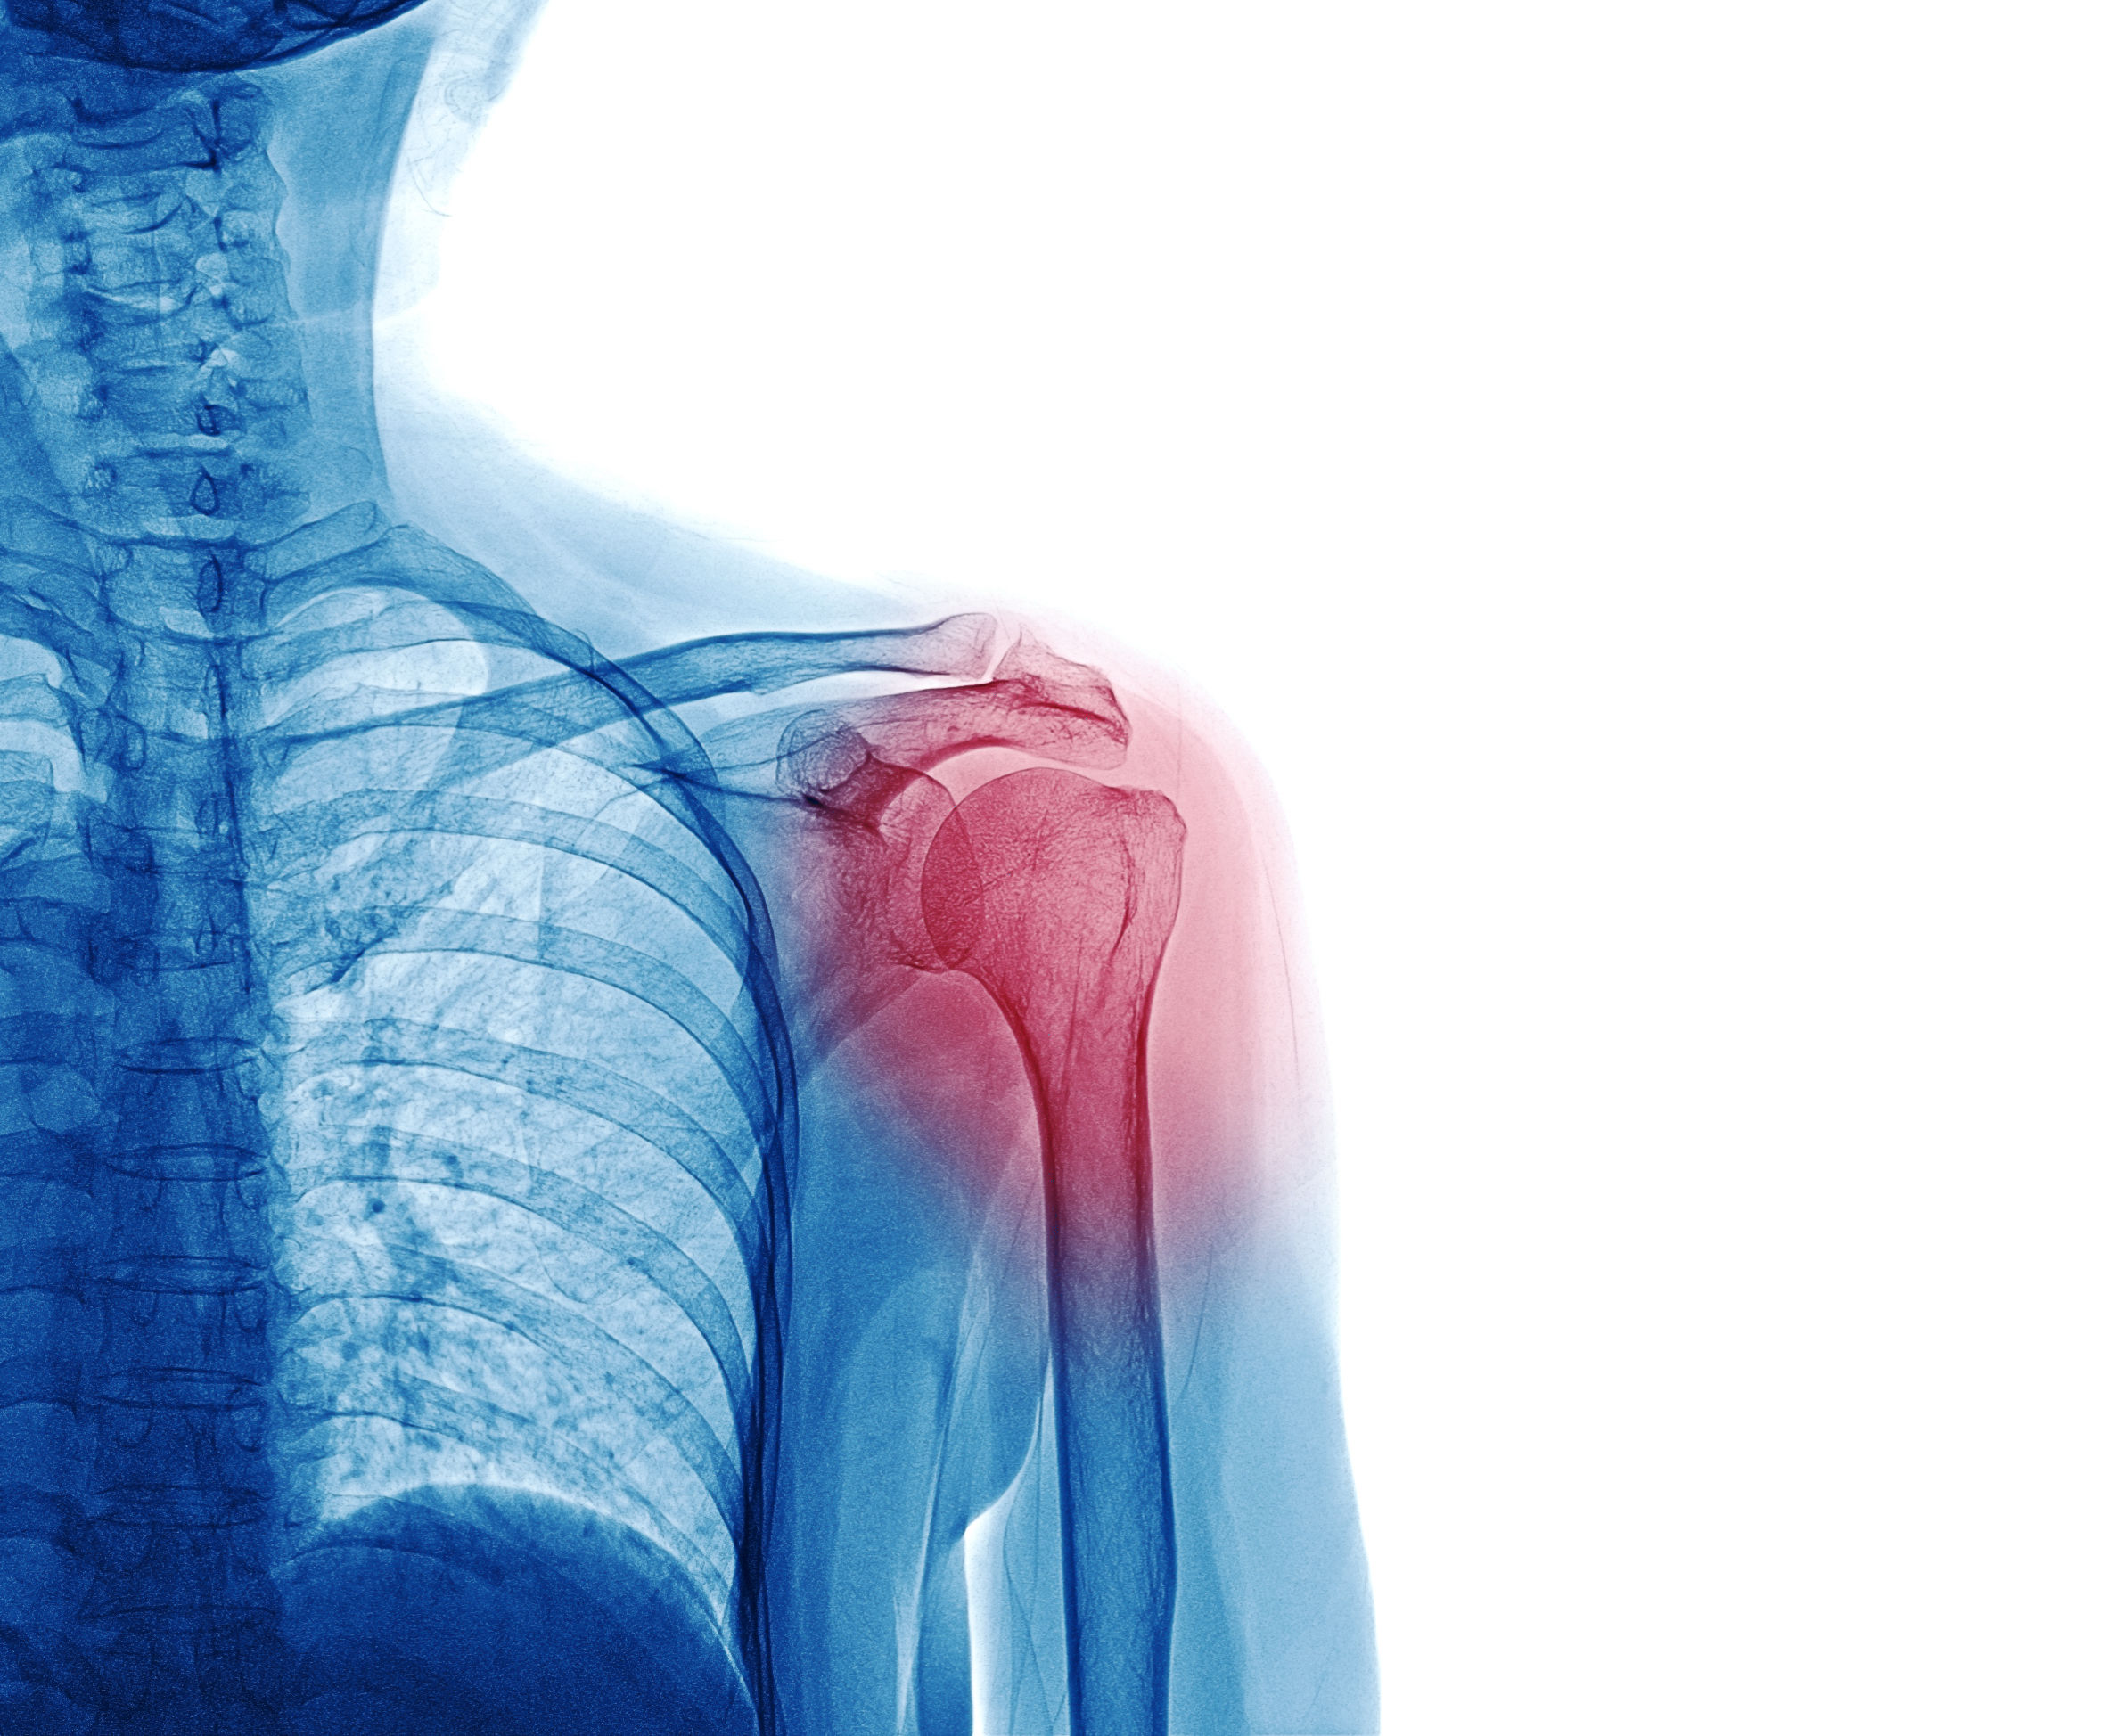

X Ray image of patient who have shoulder pain isol

Orthopedic tests such as those performed by a Chiropractor can help in diagnosis of a labral tear. MRI imaging, which is able to visualize soft tissues such as cartilage may be used to visualize a labral tear. While x-rays are not able to visualize the soft tissues and cartilage of the labrum, they are helpful to rule out other conditions and are often taken prior to more expensive MRI images.